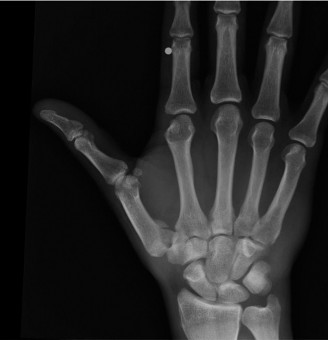

CASE 1 ### A 14-year-old patient presents with pain in the wrist after a fall. Examination reveals tenderness over the anatomical snuff box. X-ray picture is shown below (Fig. 3–1). What is the next course of treatment?

Figure 3–1(©) Sunil Thirkannad and Christine M. Kleinert.

The correct answer is (D). Injuries to the wrist with tenderness over the anatomical snuff box should raise the suspicion of a scaphoid fracture. Often, a scaphoid fracture may not be visible on initial x-ray pictures. It is prudent in such cases to suspect an “occult scaphoid fracture” and treat the patient in a splint. A repeat x-ray taken 2 to 4 weeks later can often reveal a fracture.

The same patient is seen in clinic 4 weeks later and still has persistent pain. An x-ray ordered at this time reveals the findings shown (Fig. 3–2). What is the more prudent thing to do next?

Figure 3–2(©) Sunil Thirkannad and Christine M. Kleinert.

The correct answer is (A). The x-ray reveals a fracture of the scaphoid. Healing rates are around 75% with nonsurgical treatment in adults compared to around 95% after surgery. However, since the patient is a 14-year-old child and has already been in a splint for 4 weeks, a prudent course would be to continue splinting for a further 2 to 4 weeks.